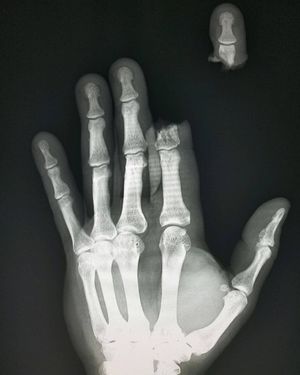

Hand x-ray showing severed finger caused by a chainsaw accident

Follow us @medicalpedia for more extreme cases!